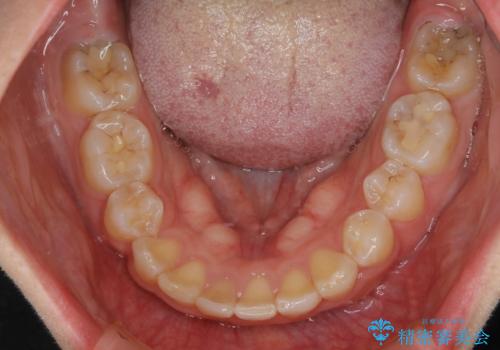

また、右下の歯が生まれつき少なく、隙間が空いている状態でした。

矯正治療でご自身の歯を移動して閉じることにしました。